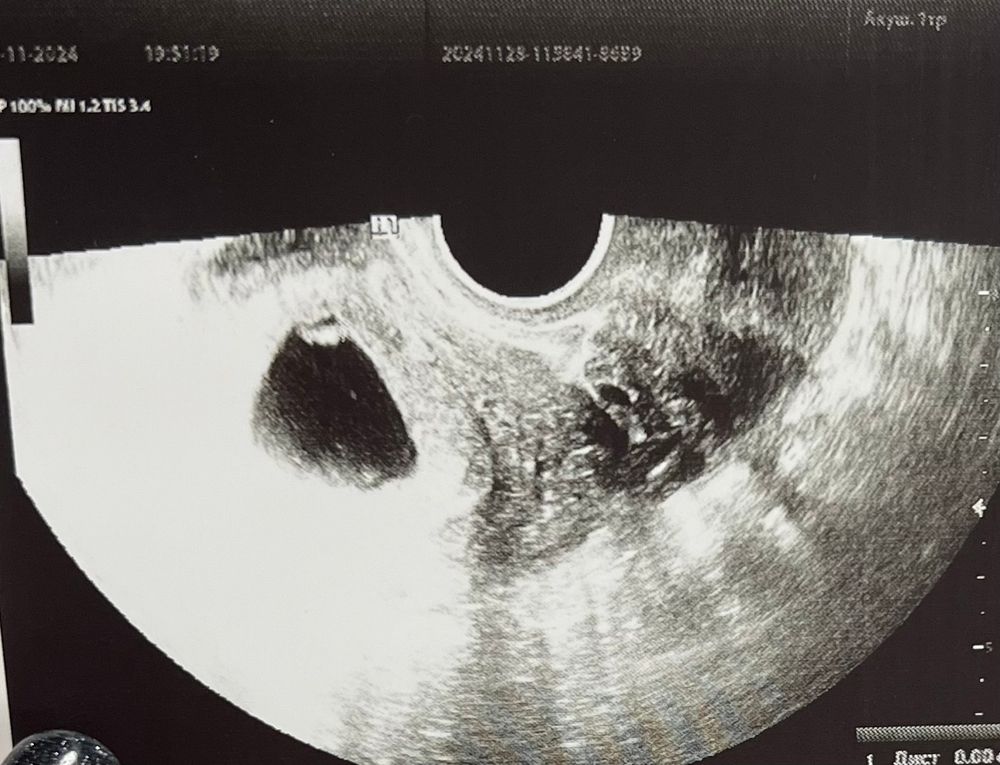

УЗИ, КТГ, доплерДевочки, 6 дней назад делала узи, ктр был 7мм, услышали чсс 122, жм 2.8.

Сегодня пошла вставать на учет, мне сделали узи и вот ктр всего 8 мм, разве может такое быть? ЧСС 156, жм 3.6. Я не понимаю как может всё вырасти кроме ктр? Спросила в врача, она мне сказала, что разные аппараты узи. Так напряглась, если честно…

Ирина, мне почему-то кажется, что сейчас неправильно. Потому что врач сказала что она вообще на таких сроках не видит смысл мерить ктр, так как можно ошибиться. И на той неделе прям надо было всматриваться, чтобы увидеть что-то, ну, по крайне мере мне нужно было всматриваться. А сегодня как только начали делать узи я уже увидела сердце, без приближений, я даже увидела что-то похожее на ручки, ну, на этом сроке, отростки просто)) а на той неделе просто пульсирующая точка была

IMPREGGY, вот такая крокозябра была в 7 недель, точно не точка. В любом случае, чсс у вас хороший, все у вас хорошо должно быть. Кто-то из узистов точно накосячил с замером или записал криво.

IMPREGGY, у вас прям домище по сравнению с моим пя)) если хотите заморочиться, можно пропорцией прикинуть

пя по узи-сколько см по фото

X ктр эмбриона-и замерить по фото

Ирина, по узи пя было 25, ктр 7. Если примерно прикинуть, то все выходит верно. Сегодня мне ПЯ не мерили вообще, но он уже не казался мне таким огромным.